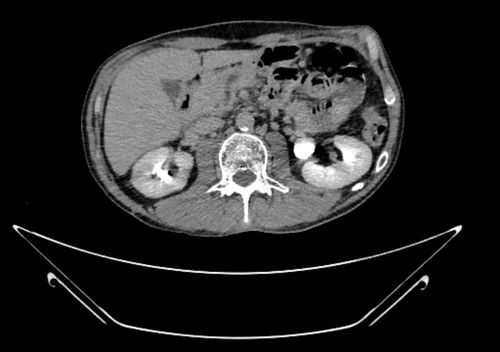

КТ органов брюшной полости. Псевдокиста поджелудочной железы у пациента после приступа острого панкреатита

Скрининговым методом в обследовании всех больных являлось ультразвуковое исследование брюшной полости. С целью более точной визуализации кист, а также проведения дифференциальной диагностики с кистозными формами опухолей поджелудочной железы всем пациентам выполнялась спиральная компьютерная томография брюшной полости.